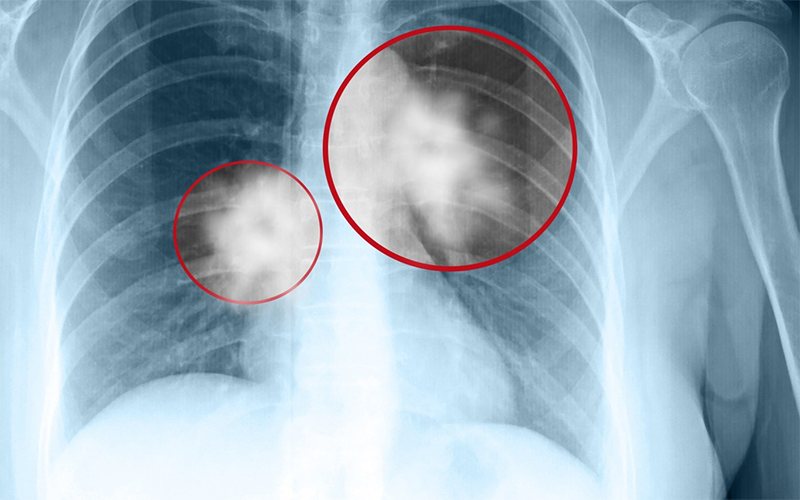

Chụp X-quang là phương pháp chiếu tia X có bức xạ cao xuyên qua các mô trên cơ thể. Một phần tia sẽ bị chặn lại và một phần sẽ bị hấp thụ, sau đó thông qua hình ảnh hiển thị lên hệ thống dữ liệu mà bác sĩ có thể chẩn đoán các tổn thương. Tuỳ vào độ dày đặc của mô mà hình ảnh hiển thị các hình thái và màu sắc khác nhau. Ví dụ, xương cho màu trắng, các mô mềm có màu xám hoặc các cơ quan chứa khí như phổ sẽ hiển thị màu đen.

Chụp X-quang thường được sử dụng để chẩn đoán các bệnh lý như viêm phổi, gãy xương, viêm khớp, các bệnh tim mạch, thần kinh, tiêu hóa, cơ xương khớp,... nhưng không thích hợp để đánh giá các mô mềm như gan, dạ dày,... vì hình ảnh không rõ nét.